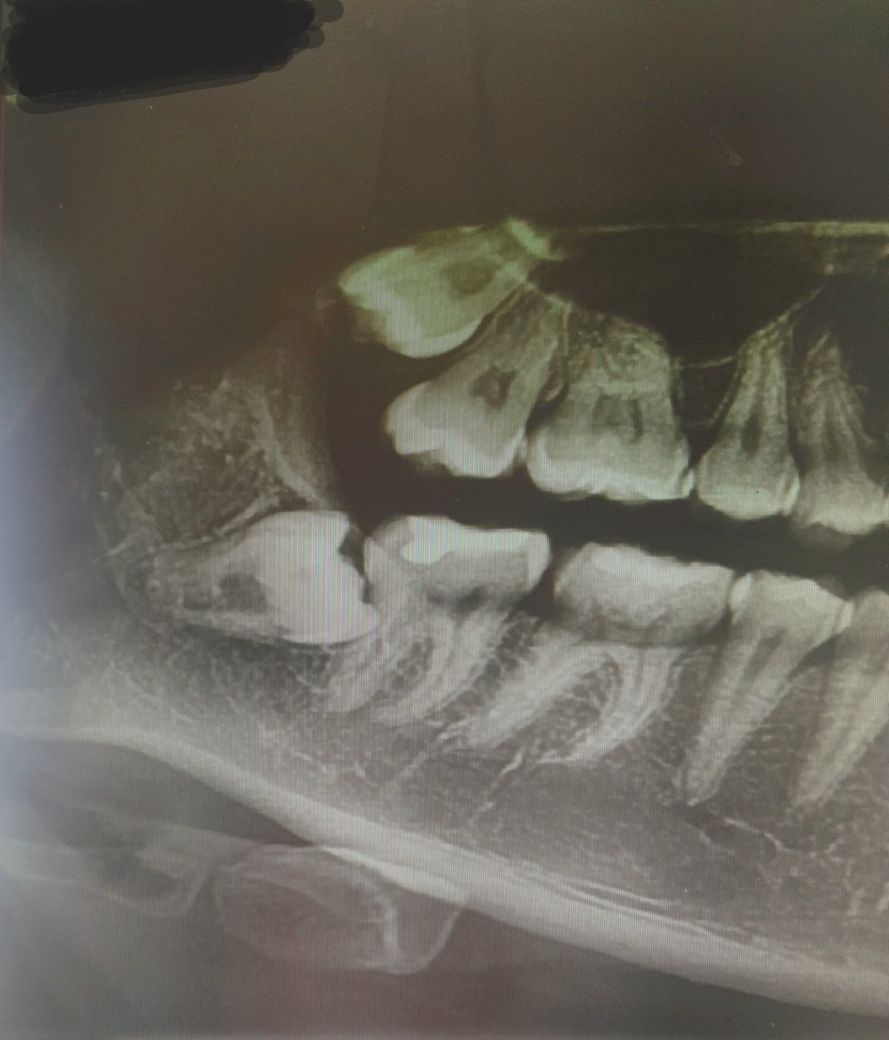

옆으로 누워있는 수평매복 사랑니 입니다.

지금 x-ray 사진상 바로앞 어금니를 밀고 있습니다. 이런 사랑니를 뽑지 않는다면 바로앞 어금니가 상하게

되니 가능한 빨리 뽑는 것이 좋습니다. 수평매복 사랑니는 치아를 부숴 조각으로 발치하니 간단한 수술에 해당합니다.

아닙니다. 뽑기는 해야 하나 매복 정도가 매우 심하고 발치 과정에서 앞쪽 어금니 손상 가능성이 높기 때문입니다. ct 사진 등을 찍어봐야 겠지만 신경과도 근접하여 발치 이후에 신경손상 가능성도 높습니다. 이러한 경우에는 발치를 하는 것을 추천드리지만 발치 과정에서 어금니 손상, 신경손상이 있을 수 있어 큰 병원에서 관리를 받으면서 발치하는 것이 좋습니다.

사랑니가 앞치아에 걸려 있는것도 걸려 있는거지만, 사랑니가 신경과거의 맞닿아 잇는듯 보입니다. 치과의사 선생님 말씀대로 일반병원에서는 뽑기 힘들수 있으며, 뽑길 원하시면 대학병원이나 사랑니 전문 병원에 가보셔야될것같습니다. 관리가 잘되시고 계시다면 발치안하셔도 되지만 염증이 생기신다면 발치를 하시는게 좋습니다.